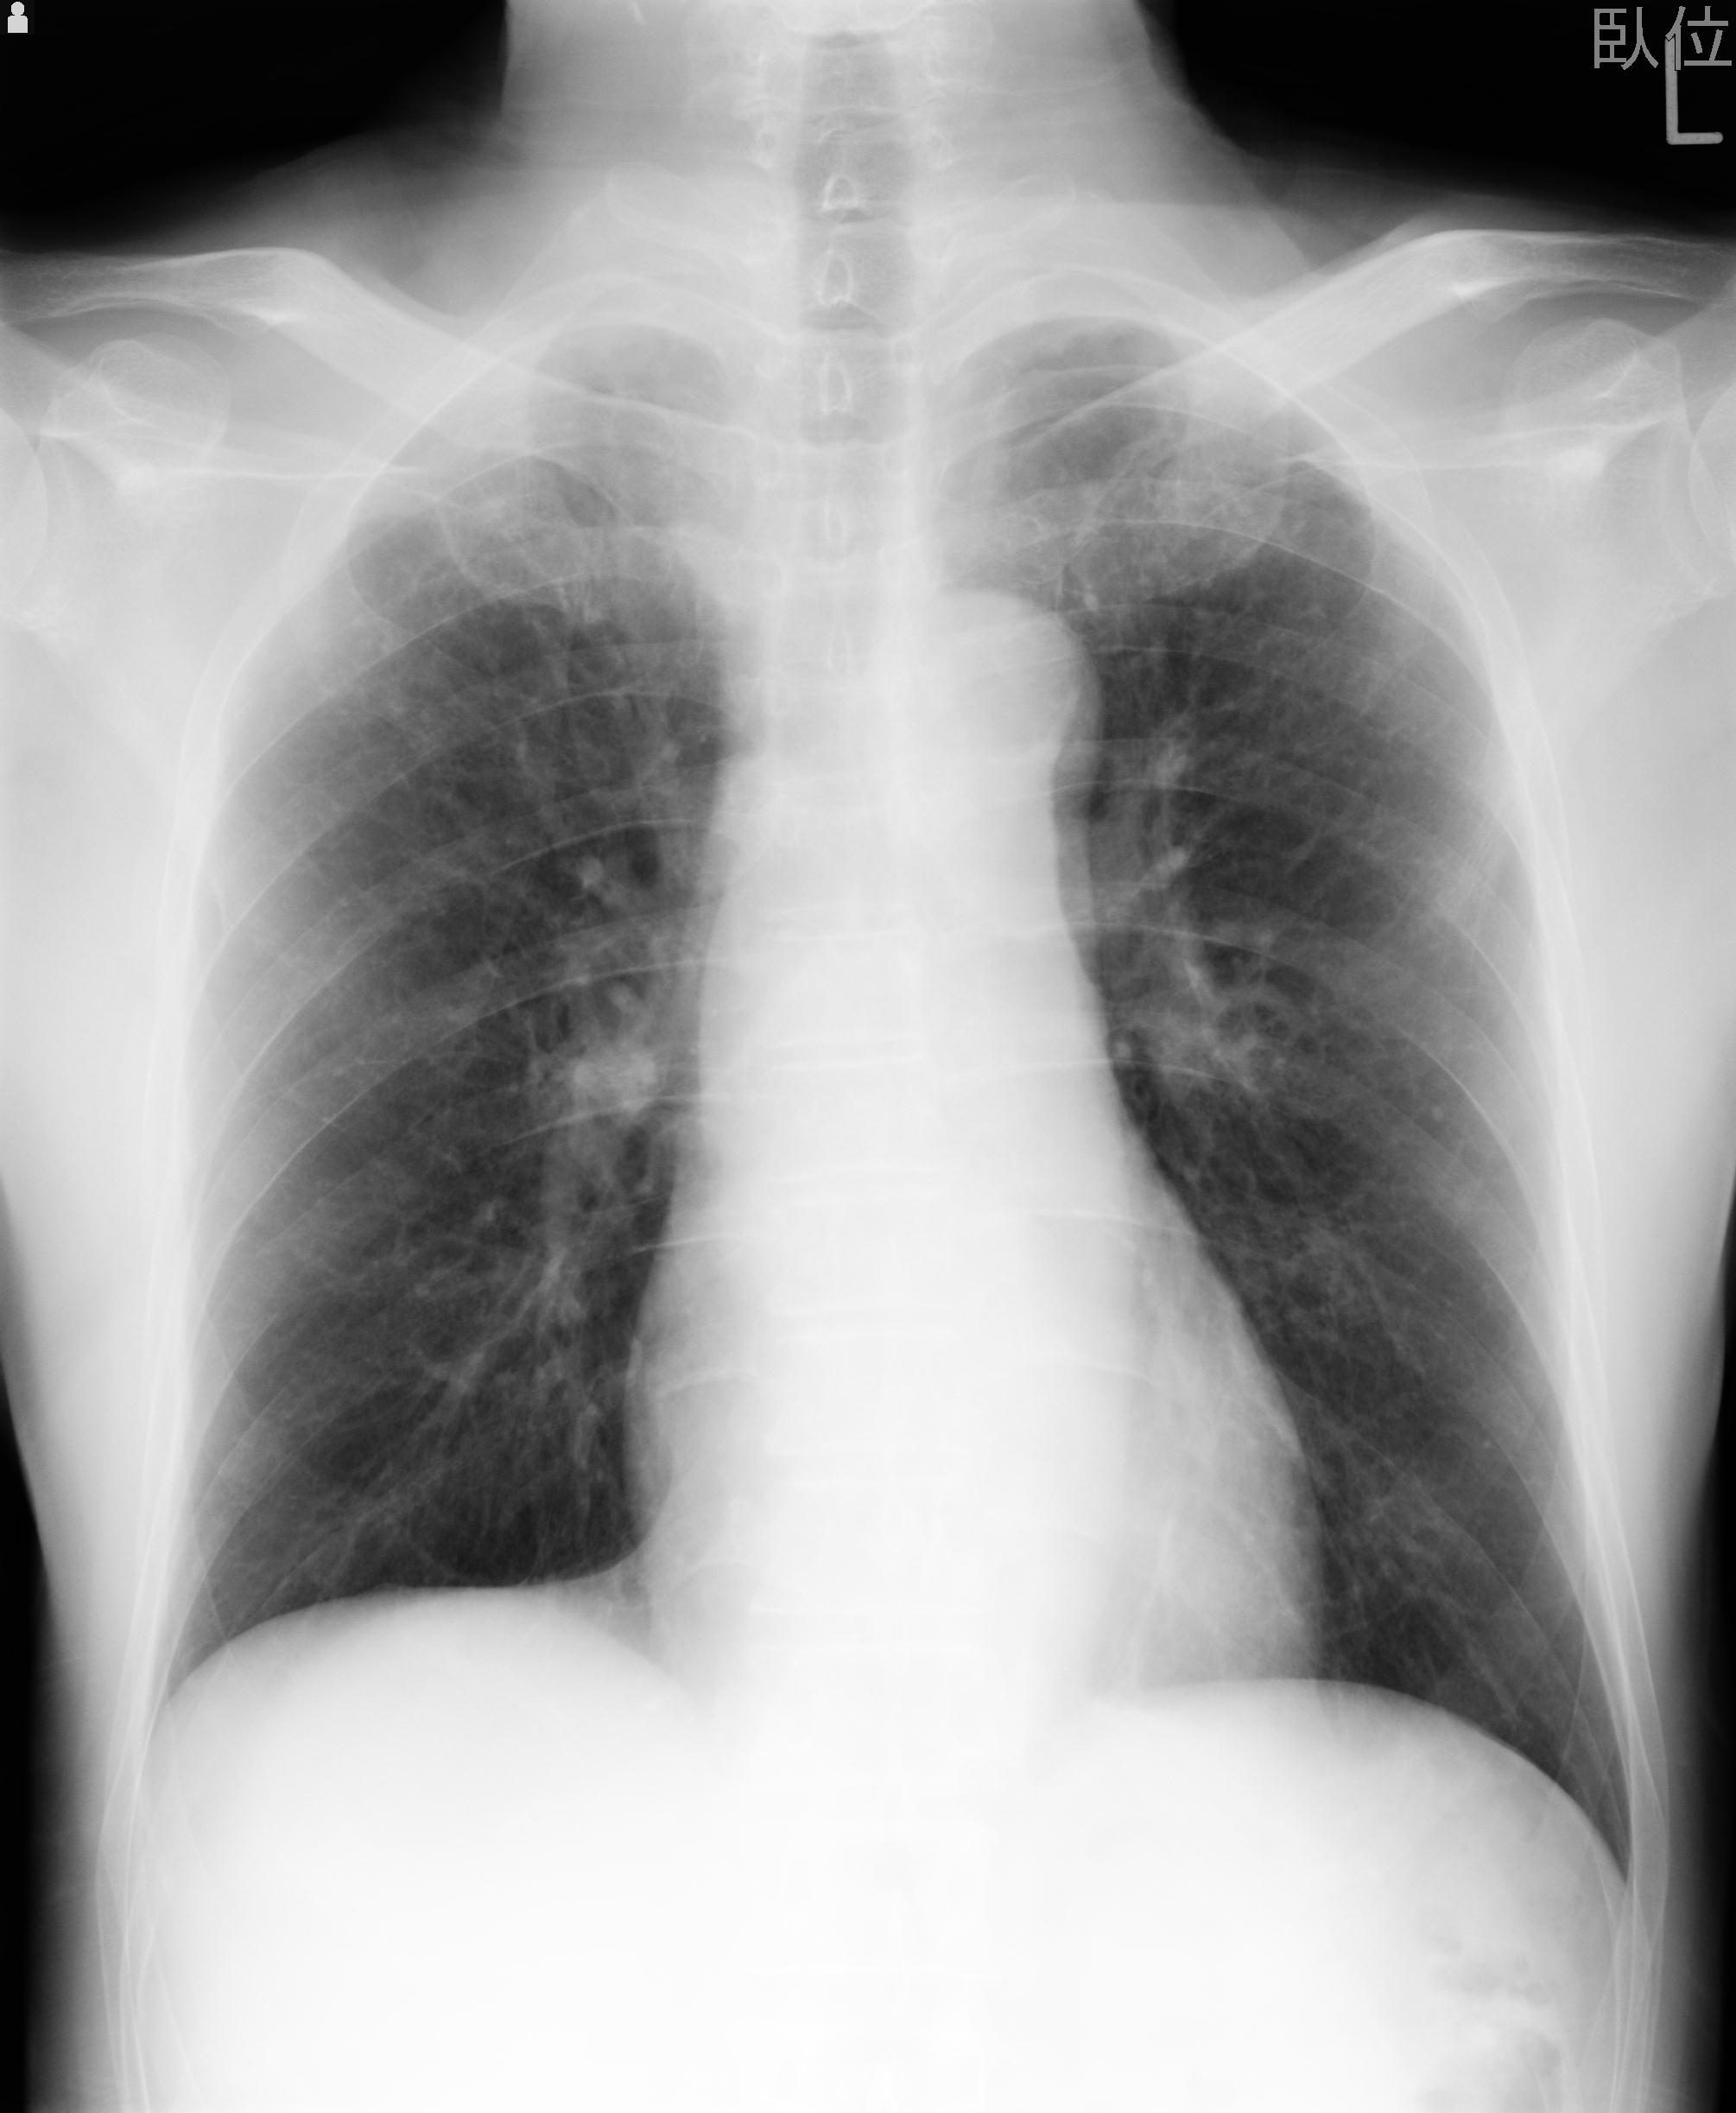

60058 3/9 11/4 右肩 2R+MRI 73歳男性 肩腱板損傷